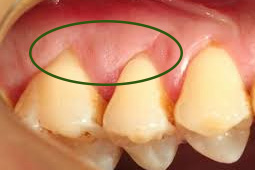

歯肉のクレフト

歯ぐきに、V字やU字型の裂け目ができてきます。